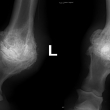

Těžká artróza ve spěnkovém kloubu

rentgenologické vyšetření